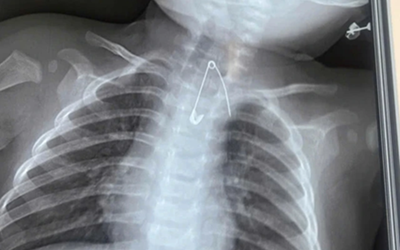

Bé trai 9 tuổi nhập viện khẩn cấp, bố mẹ "sốc" khi bác sĩ lấy ra thứ "đáng sợ" từ bụng con

Sức khỏe Thứ 6, 22/05/2026 | 02:00

Cậu bé 9 tuổi được đưa đi cấp cứu vì đau bụng dữ dội, không ai ngờ kết quả kiểm tra lại hé lộ tình trạng khiến cả bác sĩ cũng bàng hoàng.